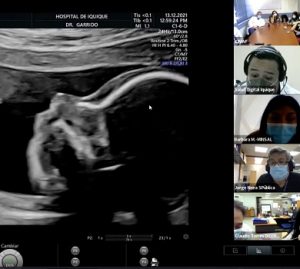

En el Hospital de Iquique realizan examen piloto para detectar Anomalías Congénitas Mayores mediante Telemedicina

Un hito en la medicina regional se llevó a cabo este lunes 13 de diciembre en el policlínico de Alto Riesgo Obstétrico del Hospital Dr. Ernesto Torres Galdames de Iquique, gracias a la estrategia piloto Pichipu -que en mapudungún significa próximo o cercano a- y cuyo objetivo es poner a disposición de la Red Pública de Salud un sistema que permita, a través de Telemedicina Sincrónica, apoyar el diagnóstico en Anomalías Congénitas Mayores (ACM) de manera integrada e interdisciplinaria.

Esta primera atención piloto, se realizó de manera conjunta entre los profesionales del Hospital y del Servicio de Salud de Iquique, un equipo multidisciplinario del hospital Sótero del Río, y los profesionales del Hospital Digital, la DIGERA y DIPRECE -integrantes de la mesa técnica ministerial en Anomalías Congénitas Mayores (ACM)- quienes siguieron el procedimiento de manera online desde Santiago.